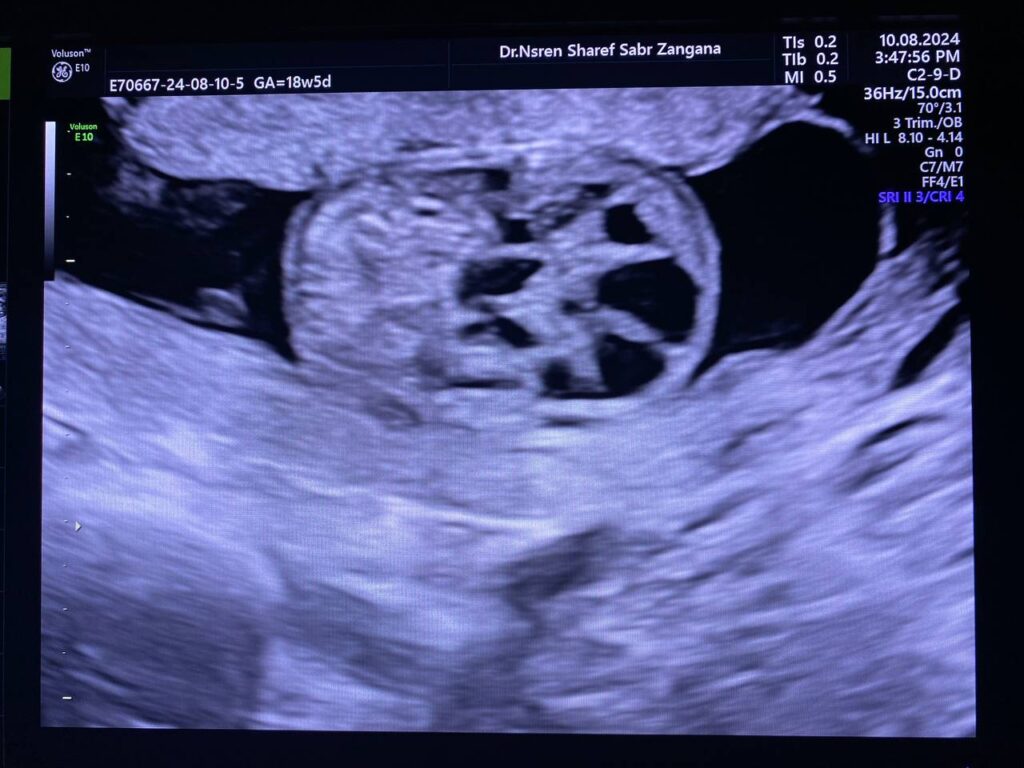

Same fetus when become about 19weeks

Right kidney enlarge in size 34x21x29mm, occupy by numerous

cysts of variable sizes, the largest 13mm , normal left kidney , polycystic ?